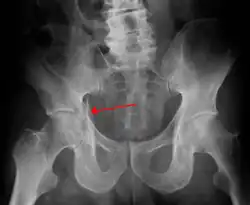

Fracture of the acetabulum

Elementary fractures

-

Posterior wall fracture as seen on 3-D CT scan -